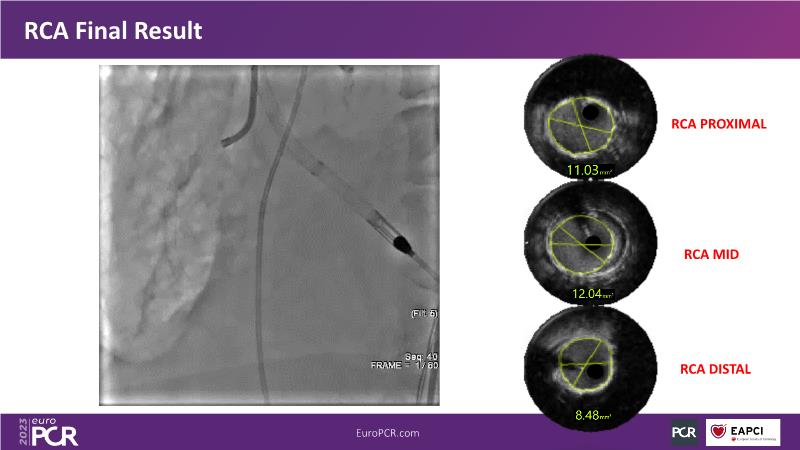

In this session, review the evolution in the use of IVL over the last few years, with a widening of the indications, observe that OCT can underestimate the number and depth of calcium fractured induced by IVL, or see that the technique is safe and effective in high-risk patients, including ACS patients, as demonstrated in real-world registries, among others!

- To understand how intravascular lithotripsy (IVL) in clinical practice has evolved over the last five years

- To evaluate the effects of IVL in different patterns of calcific coronary disease